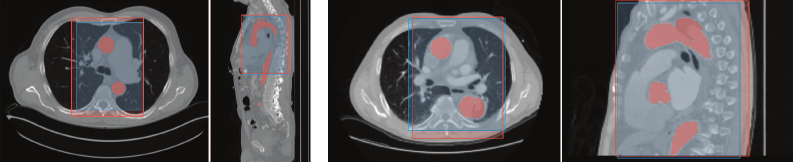

Figure 3 shows a visual comparison of the output of our detection model together with the ground truth. The results of our detection model are summarized in Table 4.

Refer to caption

Figure 3: Two examples of the detection results. Red indicates the ground truth bounding box and segmentation. Blue indicates the predicted bounding box. The mean IoU is over 0.8, with complete containment of the thoracic aorta for each image.

The mean IoU of this approach for the validation set is 0.8060.806, corresponding to a mean difference of 2.382.38 slices in all dimensions compared with the ground truth. The mean DSC for the segmentation part of this multi-task model is 0.9180.918. Regarding complete containment, this method produces bounding boxes that always contain the ROI for our complete dataset. The required computational resources to train this model with the presented data and hyperparameters is a GPU with at least 10.710.7 GB for a duration of 1919 hours. The mean inference time is 0.1460.146 seconds (not taking into account any downsampling), and the maximal required GPU memory is 2.52.5 GB.

Figure 4 shows the two mechanisms that help the final segmentation model of our cascade approach produce more accurate results more reliably: focus and image size. On the left, the raw image has a small field of view around the aorta. In this case, the region of interest is large compared to the image, and the detection step mostly centers the image around its most interesting part without dramatically reducing its size. The increased performance of our cascade approach compared to the one-step approach and nnU-Net is attributed to the more focused training based on ROIs instead of the whole images. This stems from the fact that the final segmentation of our cascade model only learned relevant features inside the ROI without needing to dedicate parts of the model to less interesting features outside of the ROI. On the right, the raw image is large compared to the ROI, leading to the detection step not only centering the image around its most interesting part but also reducing the overall image size. In addition to the focused view of the aorta, the reduction in size also allows our final segmentation model to be applied with a larger patch coverage using the same computational power. This leads to the details being handled slightly better by our cascade model than the other approaches. Additionally, the detection step also allows the cascade model to completely neglect the lower part of the image, where additional errors can occur. This is especially true in this case, where the iliac arteries are handled poorly by both the one-step model and nnU-Net, likely due to a lack of representation of these types of images in our dataset.